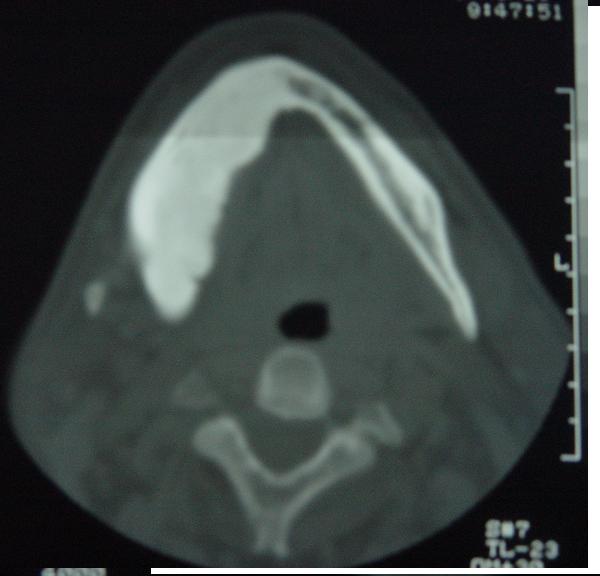

标题: CT12465:下颌骨肿瘤,请会诊 [打印本页]

标题: CT12465:下颌骨肿瘤,请会诊

发现下颌骨肿瘤近30年.逐渐增大.

考虑右侧下颌骨水平部及升部骨纤维异常增殖症可能性大。

考虑右侧下颌骨骨化性纤维瘤。